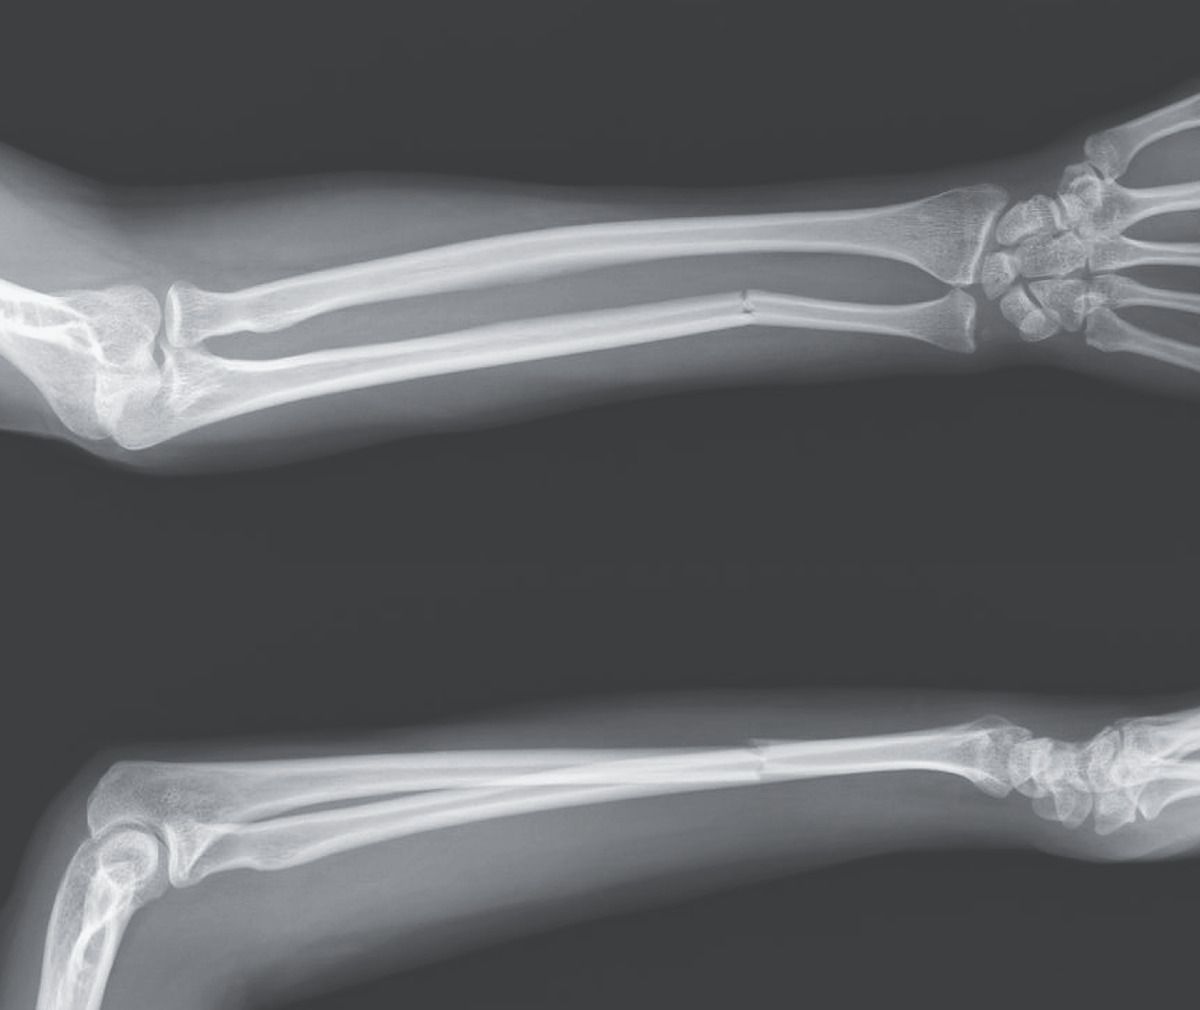

A 60-year-old left-handed woman presented to the emergency department with pain in her left forearm after having been struck by a baseball bat by her partner. On physical examination, the left forearm was swollen and tender, especially with passive pronation and supination. The overlying skin was intact, and the results of neurovascular examination were normal. No other traumatic injuries were present. Radiographs of the left forearm showed an isolated ulnar shaft fracture (upper image, anteroposterior view; lower image, lateral view). Isolated ulnar shaft fractures, also called “nightstick fractures,” result from blunt force trauma to the forearm. The injury classically occurs when the upper arm is raised in self-defense against an attack to the head or torso, such as in intimate-partner violence, as occurred in this case. Comprehensive assessments of the safety and mental health of the patient were performed, and social services were offered. The patient underwent open reduction and internal fixation of the fracture, followed by splinting, although this type of injury may be managed nonoperatively in some cases. At follow-up 10 weeks later, the patient had regained full function of her arm; she had obtained a restraining order for protection and was receiving assistance from a social worker.